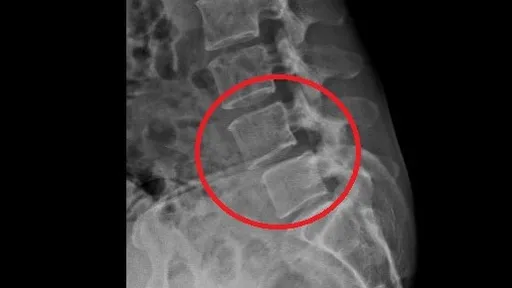

...外科醫院」院長楊椒喬指出,患者下背及肌肉痠痛劇烈,下蹲和長時間站立與行走,都有困難,右腳麻木,造成活...